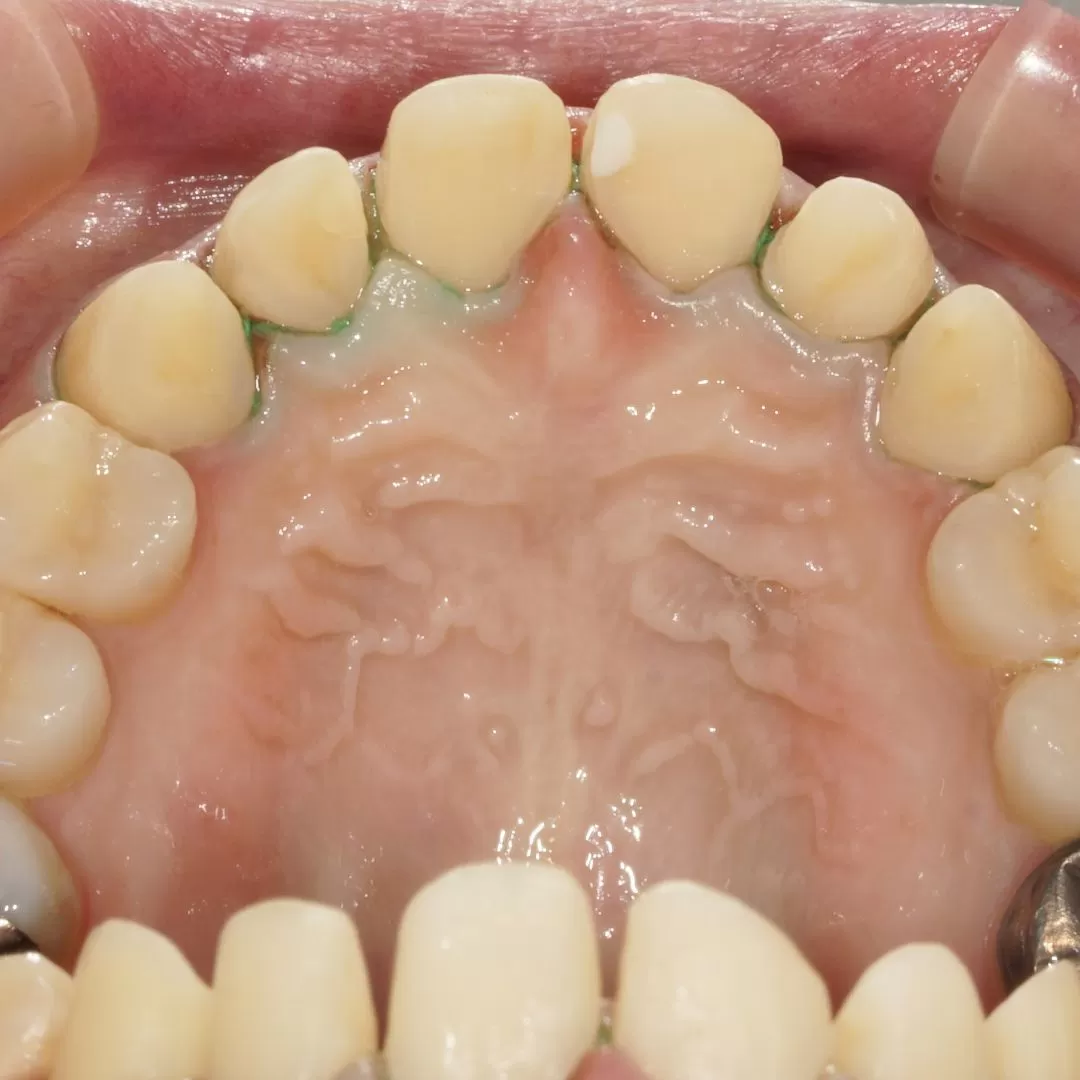

今回の症例ですがこのような状態を

このように歯茎に接する部分はぎりぎりに

このように装着してあります。

全周ラミネートべニア仕上げです。

このような努力が口臭から無縁のセラミックを作り上げるのです。